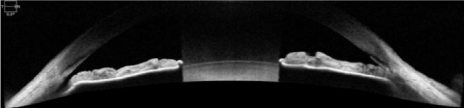

According to Adler’s, the physiological lens changes thickness from 4.0mm at age 20 to 4.7mm at 60 years of age [5].  As it increases in thickness it pushes the iris forward resulting in a shallower anterior chamber with narrowing or occluding of the anatomical angle.  An LPI may create a “by-pass” to the angle but does not significantly deepen the chamber (Figure 1 and 2).  Angles may remain narrow or occluded.   Exchanging a thicker physiological lens for a thinner IOL via lensectomy definitively deepens the angle, as shown by our study (Figure 3).  It eliminates the need for a LPI now and cataract surgery later reducing the total number of surgeries on a given eye.  It has the additional benefit of improving visual acuity and reducing ametropia.

Figure 1. OCT of a narrow angle before LPI. Note PAS in the nasal angle.

Figure 2. OCT of narrow angle after LPI. Little change in anterior chamber or angle. PAS remains.

Figure 3. OCT of narrow angle after LPI and CE. Anterior chamber and angle are visibly deeper. PAS remains.